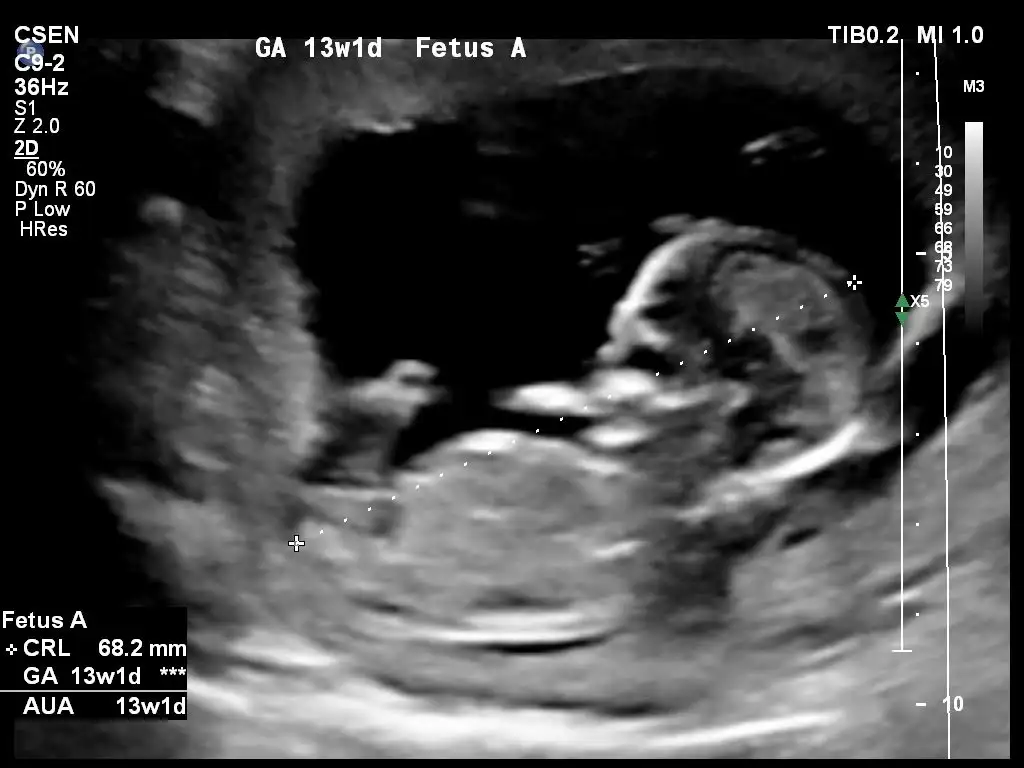

Merhaba Ikra meyra canım, bir tahmin alabilir miyim ben de 13+2 olduk.

Eklentiler

• 20201021_114201.webp

23,3 KB · Görüntüleme: 67

• 20201021_114209.webp

23,7 KB · Görüntüleme: 55

• 20201021_114216.webp

18,4 KB · Görüntüleme: 84